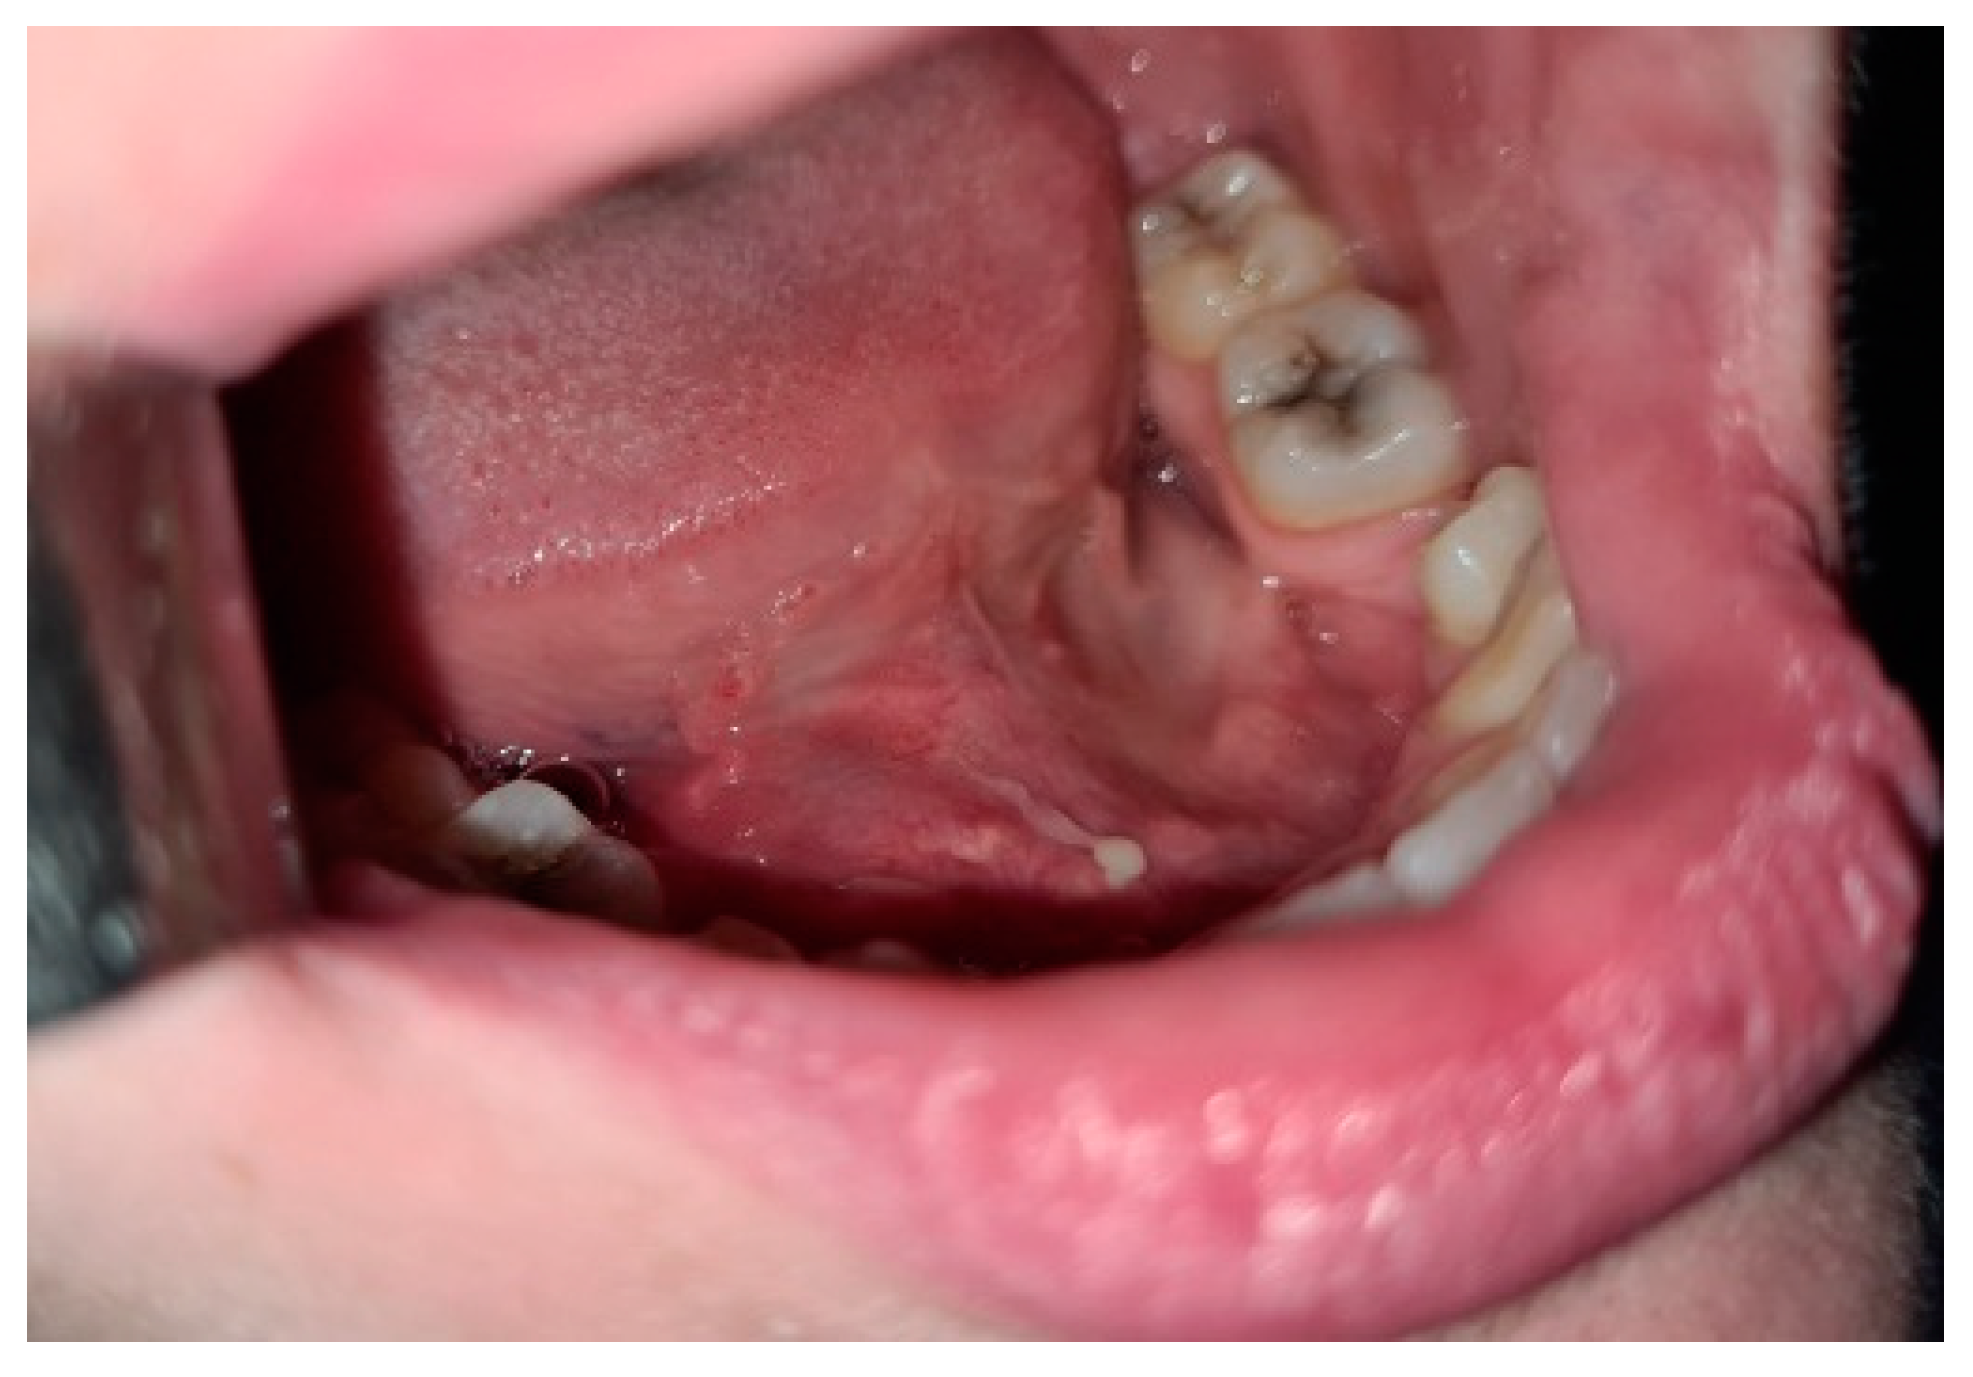

2. Case Report